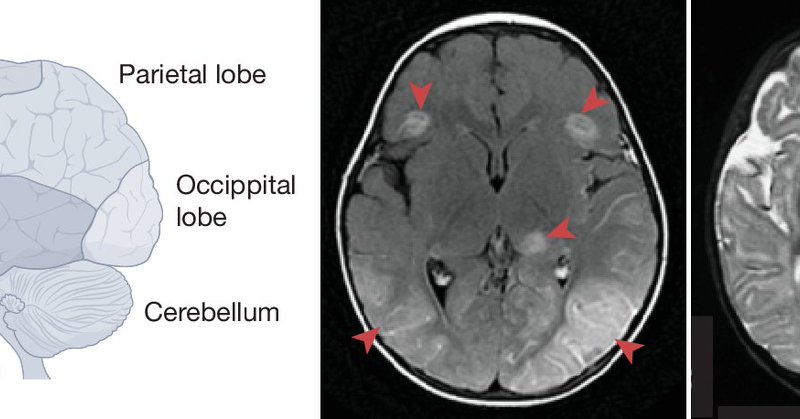

The brain injury 1 year post-Covid hospitalization, systematically assessed with MRI (reduced grey matter), biomarkers, and cognitive deficits "equivalent in magnitude to aging from 50 to 70 years of age." https://t.co/ZJAShcRvOb @NatureMedicine @gkwood3 @BenedictNeuro